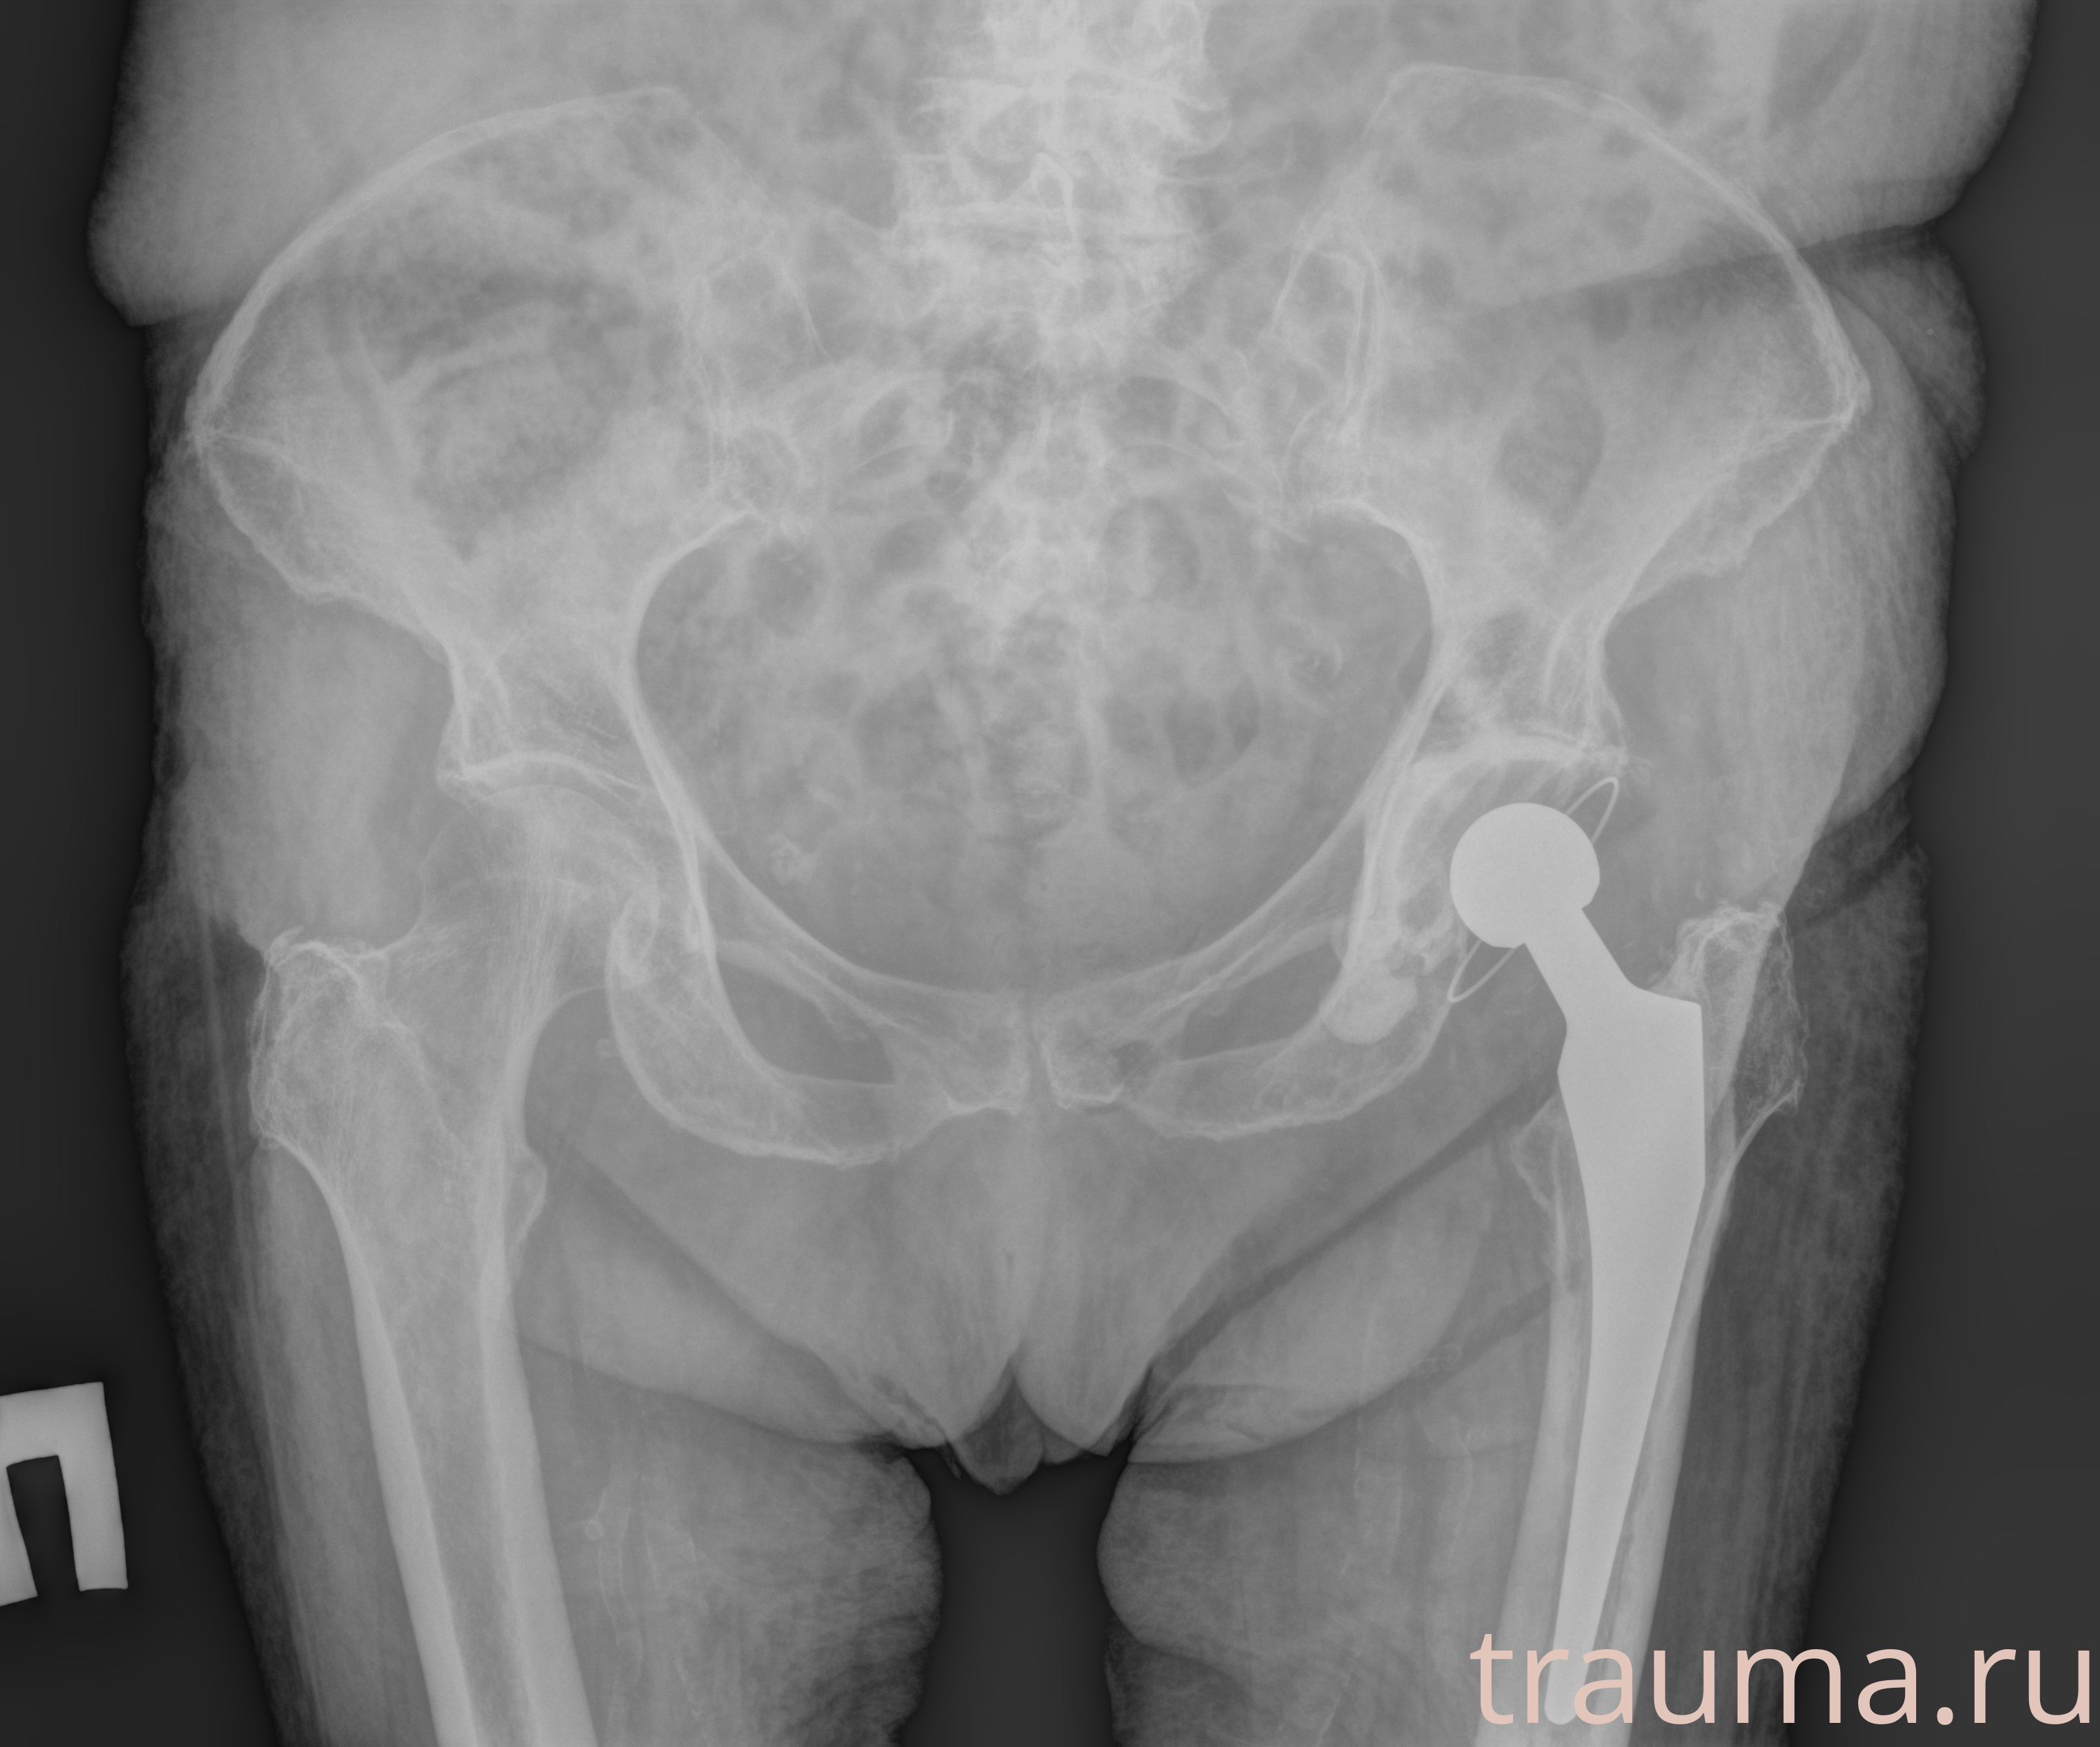

Рентген на дому: по вашему адресу приезжает врач-рентгенолог, травматолог-ортопед с мобильным рентгеновским аппаратом, проводит диагностику травмы или заболевания, делает необходимые рентгенограммы, дает рекомендации по дальнейшему лечению. Получить качественные снимки в домашних условиях возможно благодаря уникальной методике, разработанной МосРентген Центром для института  Склифосовского

при переломе шейки бедра и пневмонии от компании МосРентген Центр - партнера Института имени Склифосовского